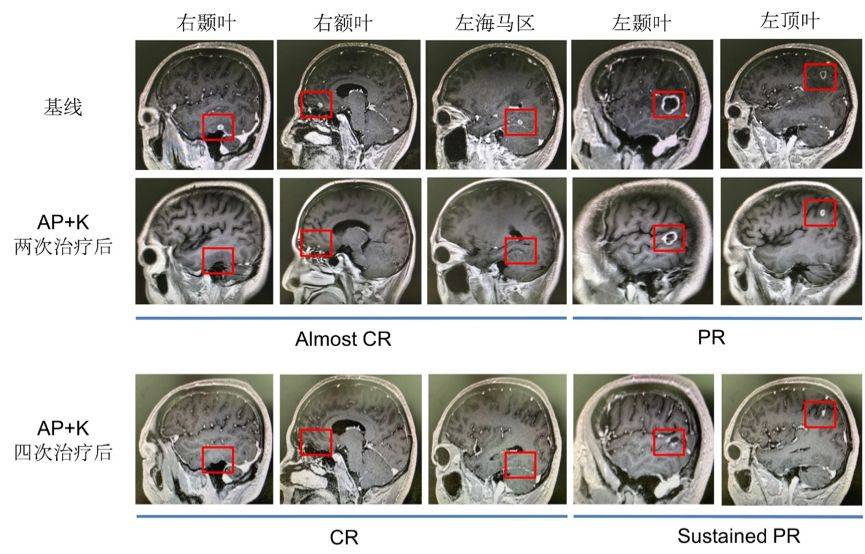

两次化疗+ pembrolizumab后,我们发现患者左侧颞叶、顶叶环形强化结节较前减小,周围水肿带范围较前减小。左侧海马区、右侧颞叶及额叶,强化结节较前明显减小,部分呈点状、部分显示不清。胸部CT提示肺部原发灶变化不明显。

继续这个治疗方案,于2019年4月10日至2019年5月14日对患者再行2次K药联合化疗治疗。再次行头颅增强核磁结果提示:左侧颞叶、顶叶强化结节较前减小,周围水肿带范围较前减小。原左侧海马区、右侧颞叶及额叶、右侧小脑半球强化结节未见明确显示。胸部CT结果提示右上肺结节较前减小(约25.7%),但未达到PR。

图4. 头颅双倍剂量增强MRI(基线以及两次和四次联合治疗后)